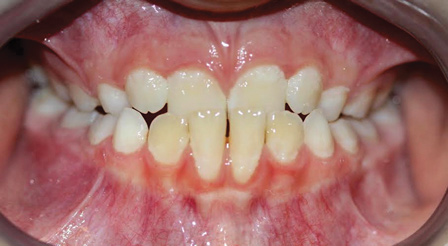

Fig 9. Anteroposterior view of class II (Fig 9) and class III (Fig 10) malocclusion. Arrows indicate positions of the mesial maxillary cusp and embrasure between the mandibular molar cusps. In class II malocclusion the maxillary molar is more anteriorly positioned, while in class III the mandibular molar is more anteriorly positioned.

Figure 9

Fig 10. Anteroposterior view of class II (Fig 9) and class III (Fig 10) malocclusion. Arrows indicate positions of the mesial maxillary cusp and embrasure between the mandibular molar cusps. In class II malocclusion the maxillary molar is more anteriorly positioned, while in class III the mandibular molar is more anteriorly positioned.

Figure 10

Class II malocclusions (Figure 9) may be treated to reduce risk of dental trauma of protruding maxillary incisors or to break a lip trap habit. Some devices used for this purpose include headgears or functional appliances. Many orthodontists may wait to treat class II malocclusions in the permanent dentition because studies find inconclusive evidence of the effectiveness of phase I treatment.28 Early intervention is a strong consideration for class III malocclusion (Figure 10), with the goal of avoiding surgical treatment for either an adolescent or adult. This approach takes into consideration psychological-social concerns as well with regard to balancing facial disproportions and correcting the appearance of an "underbite" and/or prominent lower jaw.29 However, because there is a genetic component, surgery cannot be ruled out as a comprehensive treatment option. An early intervention would include facemask therapy with RPE to orthopedically protract and widen the upper jaw.